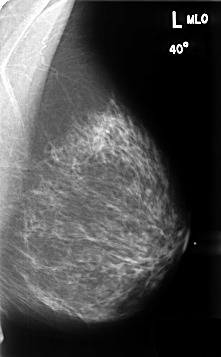

B_3459_1.LEFT_MLO

LEFT_MLO LINES 4640 PIXELS_PER_LINE 2872 BITS_PER_PIXEL 12 RESOLUTION 50 NON_OVERLAY